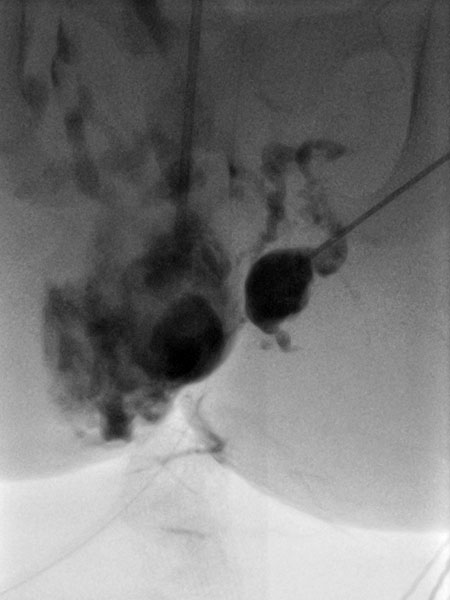

Nach Sicherung der Diagnose erfolgte jetzt die Therapie in Form einer Bleomycin Elektrosklerotherapie. Hierzu wurde die venöse Malformation zunächst mit jeweils einer Nadel unter Ultraschallsteuerung auf beiden Seiten punktiert und mit Kontrastmittel injiziert. Gute Nadellage, es finden sich keine größeren Drainagevenen.

Über die beiden liegenden Nadeln wurde jetzt insgesamt 0,75 mg Bleomycin (eins zu drei in Kontrastmittel verdünnt) in die venöse Malformation direkt intraläsional injiziert. Anschließend auf beiden Seiten insgesamt zusammen 11 Applikationen einer reversiblen Elektroporation mit der Fingerelektrode mit 15 mm aktiver Nadellänge.